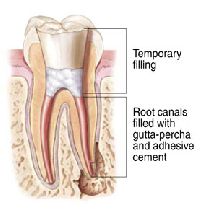

Root Canal Sealing

All canals have different shapes and for this purpose we use a filling material that can be compressed and pushed into all the spaces that may be present in the canal,which makes it impossible for microbial activity to regenerate in the tooth ensuring total success of the root canal treatment. For this we use a special unit called the System B which is the highest standard of completely and totally sealing off the root canal